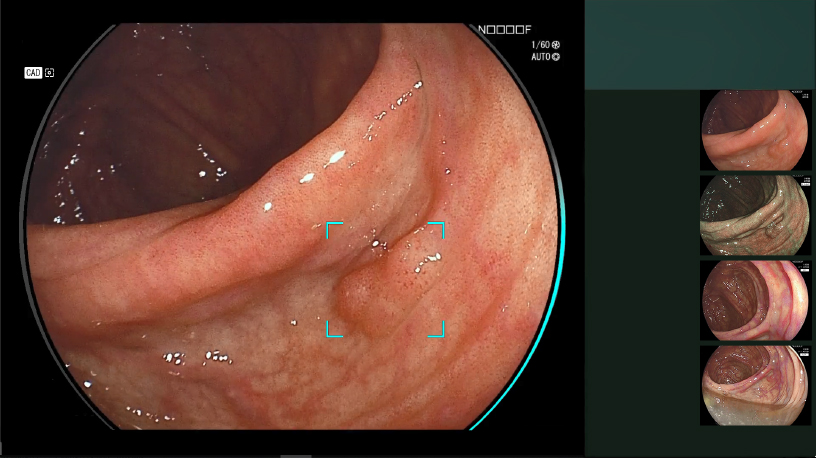

照射した光と画像処理を組み合わせる「マルチライトテクノロジー」により、粘膜表層の微細な血管や構造を強調するなど、目的に応じた観察画像を作り出す4色のLED光源搭載の内視鏡システム『ELXEO7000』を導入しています。

通常の観察画像です。